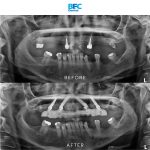

เคสรากเทียมทั้งปาก

รากเทียมทั้งปากด้วยระบบ Digital พร้อมมีฟันใหม่ได้ภายใน 1 วัน